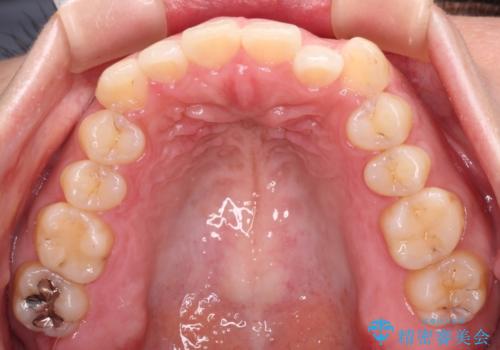

【モニター】カリエール・ディスタライザーを併用した八重歯のインビザライン矯正

- 前歯の叢生と八重歯を気にして来院された患者様です。

目立たない装置を希望とのことで、インビザラインにて矯正治療を行うこととしました。

インビザライン単体で改善することも可能ですが、八重歯とその後方にある歯列を確実移動させないと、上下正中がずれてしまう可能性があります。

インビザライン単体での治療ではなく、カリエール・ディスタライザーという補助装置を併用して、より確実性を上げることとしました。

補助装置で八重歯を解消しながら、並行してインビザラインで歯列を整えることとしました。

カリエールディスタライザーを併用したことで、すっきりとした口元になり、上下の正中を合わせることができました。